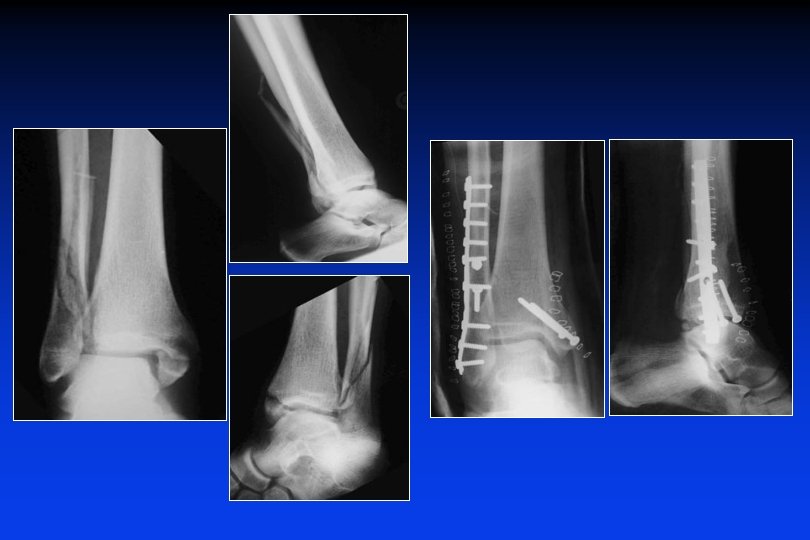

Fractura en rotación externa supra-ligamentaria Osteosíntesis del peroné peron por medio de una placa. Reducción de la diastasis. Sutura del LLI

Fractura en rotación externa supra-ligamentaria Osteosíntesis del peroné por placa y tornillos. Reducción de la diastasis Tibio-peroneo distal por medio de 1 tornillo. Sutura del LLI